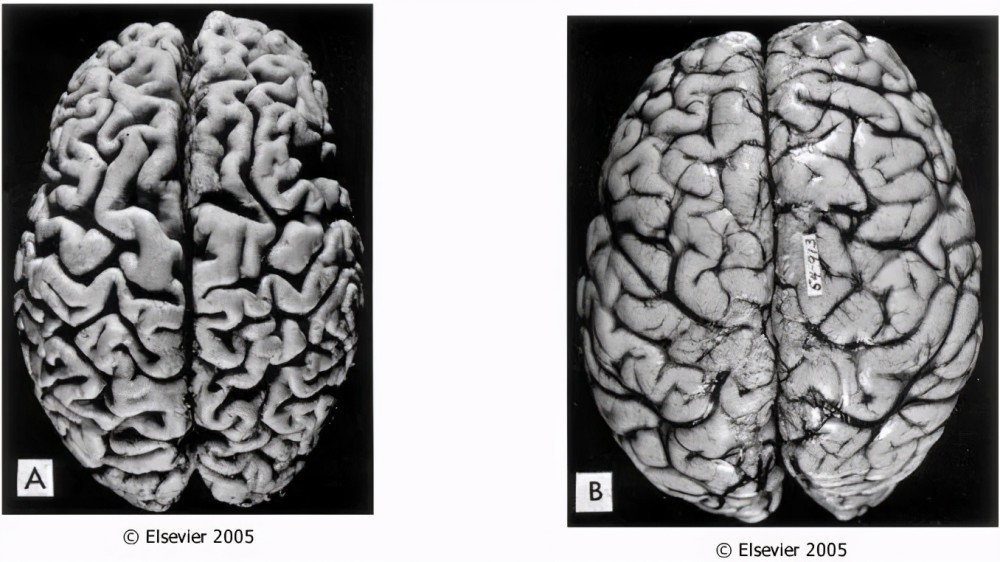

(左:萎缩脑/右:正常脑)